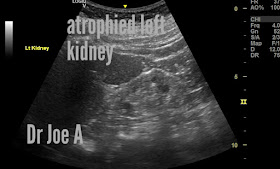

All the signs of medical renal disease involving the left kidney.

The left kidney is barely visible on ultrasound.

The left kidney appears smaller in size than the right kidney.

The kidney tissue appears more echogenic (brighter) than normal, which may indicate the presence of scar tissue or an increase in fat content.

The normal boundary between the outer (cortex) and inner (medulla) regions of the kidney appears indistinct, suggesting a loss of cortico-medullary differentiation.

The kidney may in some cases appear lobulated or have an irregular shape due to scarring or other changes in the tissue.

Blood flow to the kidney is reduced, as evidenced by a decrease in renal artery size and flow velocity.